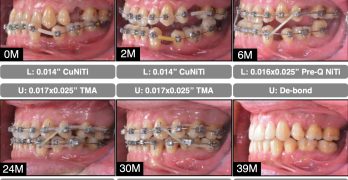

Transformación Estética y Funcional en Maloclusiones Clase II División 2 con el Carriere Motion

El artículo que compartimos el día de hoy se llama Management of Class II division 2 patient treated with Carriere … [Leer más...] acerca de Transformación Estética y Funcional en Maloclusiones Clase II División 2 con el Carriere Motion